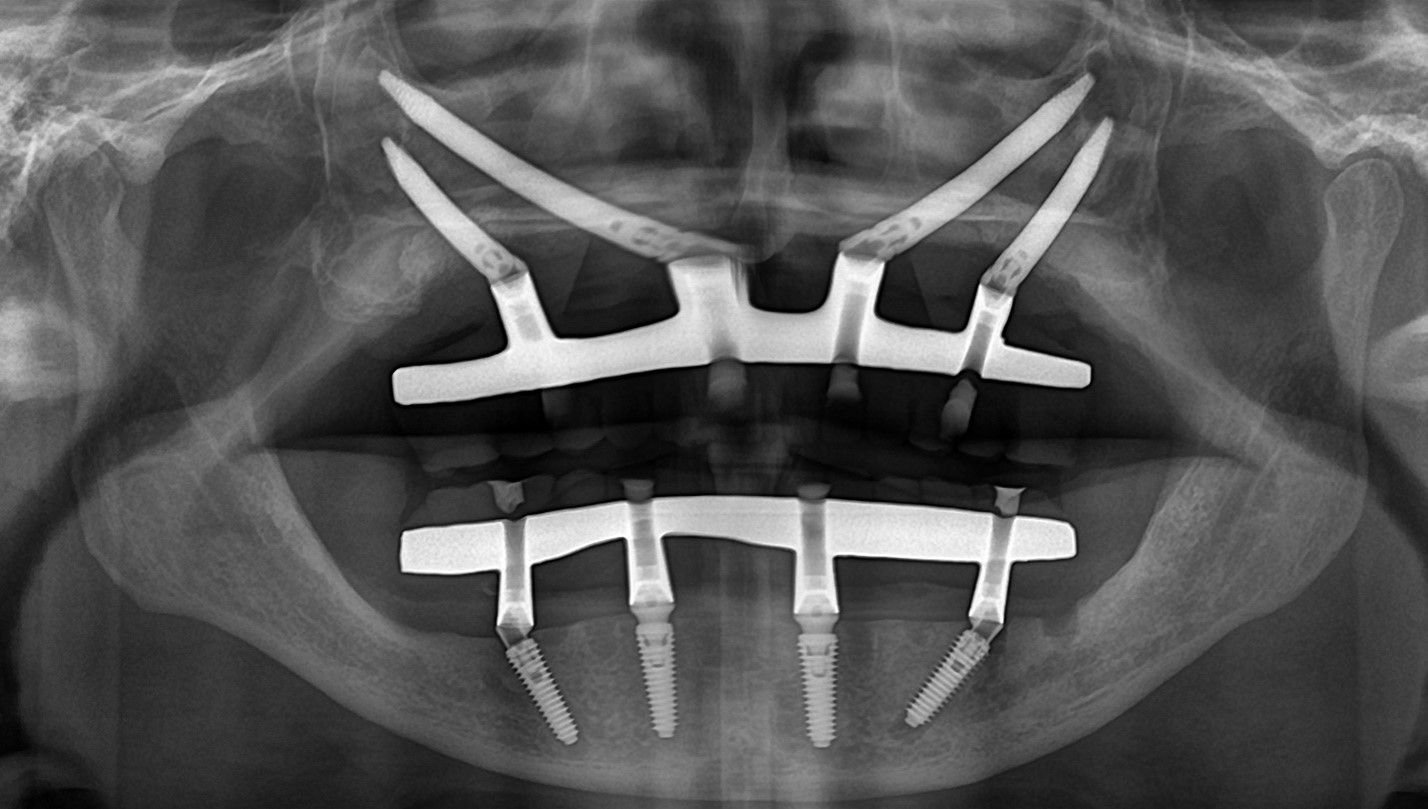

Zygoma Implant là loại implant dài hơn implant thông thường (30 – 55 mm), được đặt vào vùng thân xương gò má – vùng xương cứng, dày và ít tiêu theo thời gian.

2. Lập kế hoạch phẫu thuật kỹ thuật số

- Xác định:

- Vị trí đặt implant

- Hướng và chiều dài implant

- Tối ưu phân bố lực nhai, giảm áp lực lên mô mềm

3. Phẫu thuật cấy ghép

- Implant được đặt chính xác theo kế hoạch kỹ thuật số